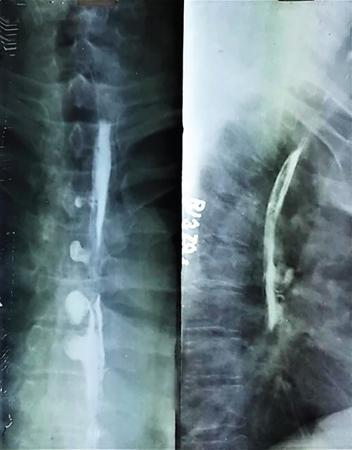

Single contrast barium study (Fig. 7.4.5.1), CECT (Figs. 7.4.5.2 and 7.4.5.3).

Fig 7.4.5.1 Barium study of the patient.

Fig 7.4.5.2 CECT of the patient.

Fig 7.4.5.3 CECT of the patient.

Observations

Barium study shows large filling defect in the antrum forming acute angles with the wall. Undulating contour is seen along greater curvature with ulceration of overlying mucosal irregularity.

CECT shows a large lobulated mass involving lesser curvature and antrum with marked wall thickening along distal greater curvature.

Diagnosis

Carcinoma stomach.